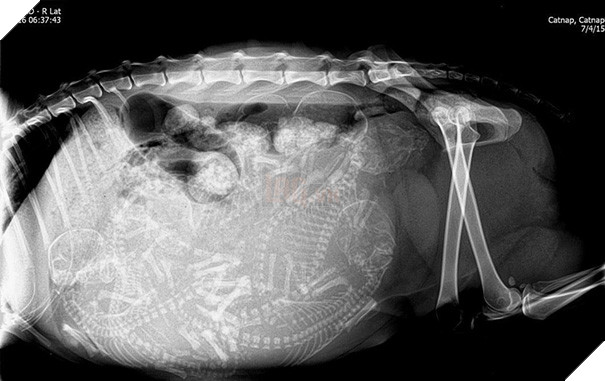

Một bà mẹ mèo đang mang thai. Thời gian thai kỳ của mèo khoảng 56 - 71 ngày, trung bình kéo dài khoảng 67 ngày và chúng có thể "sản xuất" 3 - 4 lứa mỗi năm.

Một hình ảnh khác về mèo mang thai. Có những loài vật mang thai 14 ngày là sinh nở, nhưng cũng có loài động vật cần 23 tháng để "mang nặng đẻ đau" khúc ruột của mình.